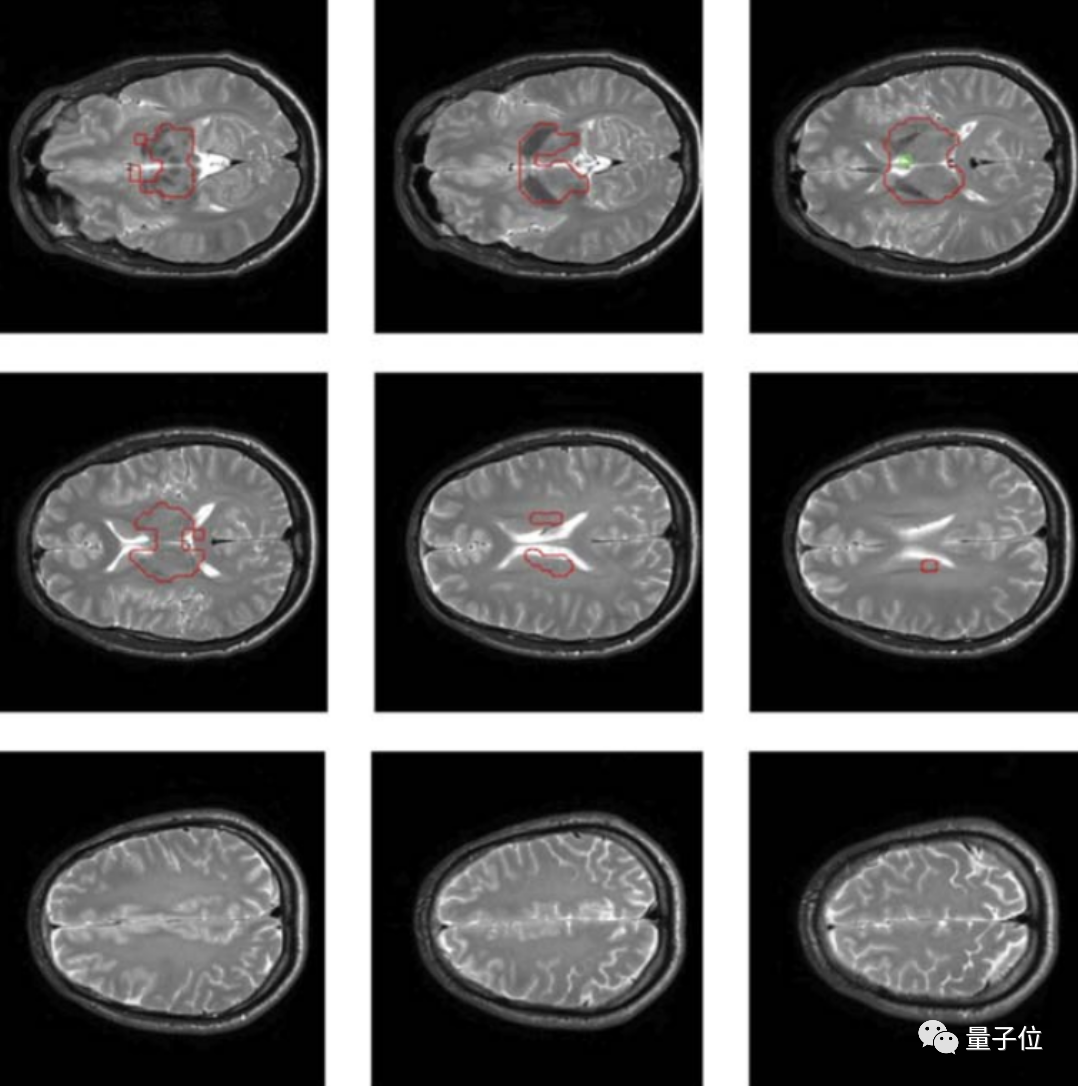

具体来说,这项研究采用了一种基于多量子相干的磁共振成像方法。

磁共振成像能基于核磁共振原理,检测构成物体原子核的情况,进而推断组成物质的分布、种类、数量、化学环境等,据此绘制成整个物体内部的结构图像。

通过这种方法,在测量了40个人(18~46岁之间)的大脑信号后,研究人员在大部分人的大脑区域中都测量出了一种诱发脑电信号。